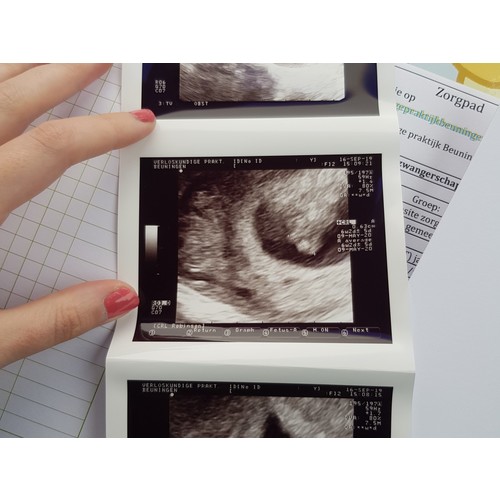

Wij hebben bij zes weken en 2 dagen ook echo gehad en konden het hartje zien kloppen.

Vandaag een echo gehad en ze schat in dat ik tussen de 5,5-6 weken zwanger ben. Uitwendig zag ze wel wat, maar inwendig was het beter te zien en hebben we het hartje zien kloppen.